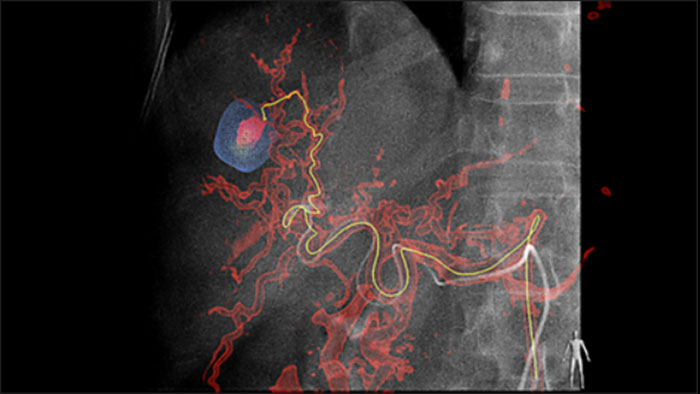

Automatic Feeder Detection solution can significantly improve feeding artery detection. EmboGuide supports you in maximising the efficacy of your TACE procedures as it potentially enhances your sensitivity, reduces false positives and maximises inter-reader agreement1. EmboGuide also provides efficient, workflow-based live 3D guidance with automatic feeder detection1.

Adoption of chemo/radioembolisation techniques such as TACE and SIRT drives the need for standardisation and efficiency. Case after case, you must reliably and consistently locate the tumor(s), identify all feeder vessels, and plan/execute the appropriate interventional approach. Our Automatic Feeder Detection solution can significantly improve feeding artery detection compared to using Cone Beam CT alone. EmboGuide supports you in maximising the efficacy of your TACE procedures as it potentially enhances your sensitivity, reduces false positives and maximises inter-reader agreement.1

The ability to detect and differentiate hepatic nodules and identify tiny feeder vessels is critical to determining proper therapy. Navigating to the region of interest by reaching all feeders, while remaining selective to the lesion, increases the opportunity for success. Confirmation of treatment endpoint and treatment success while the patient is still on the table boosts clinical outcome confidence.